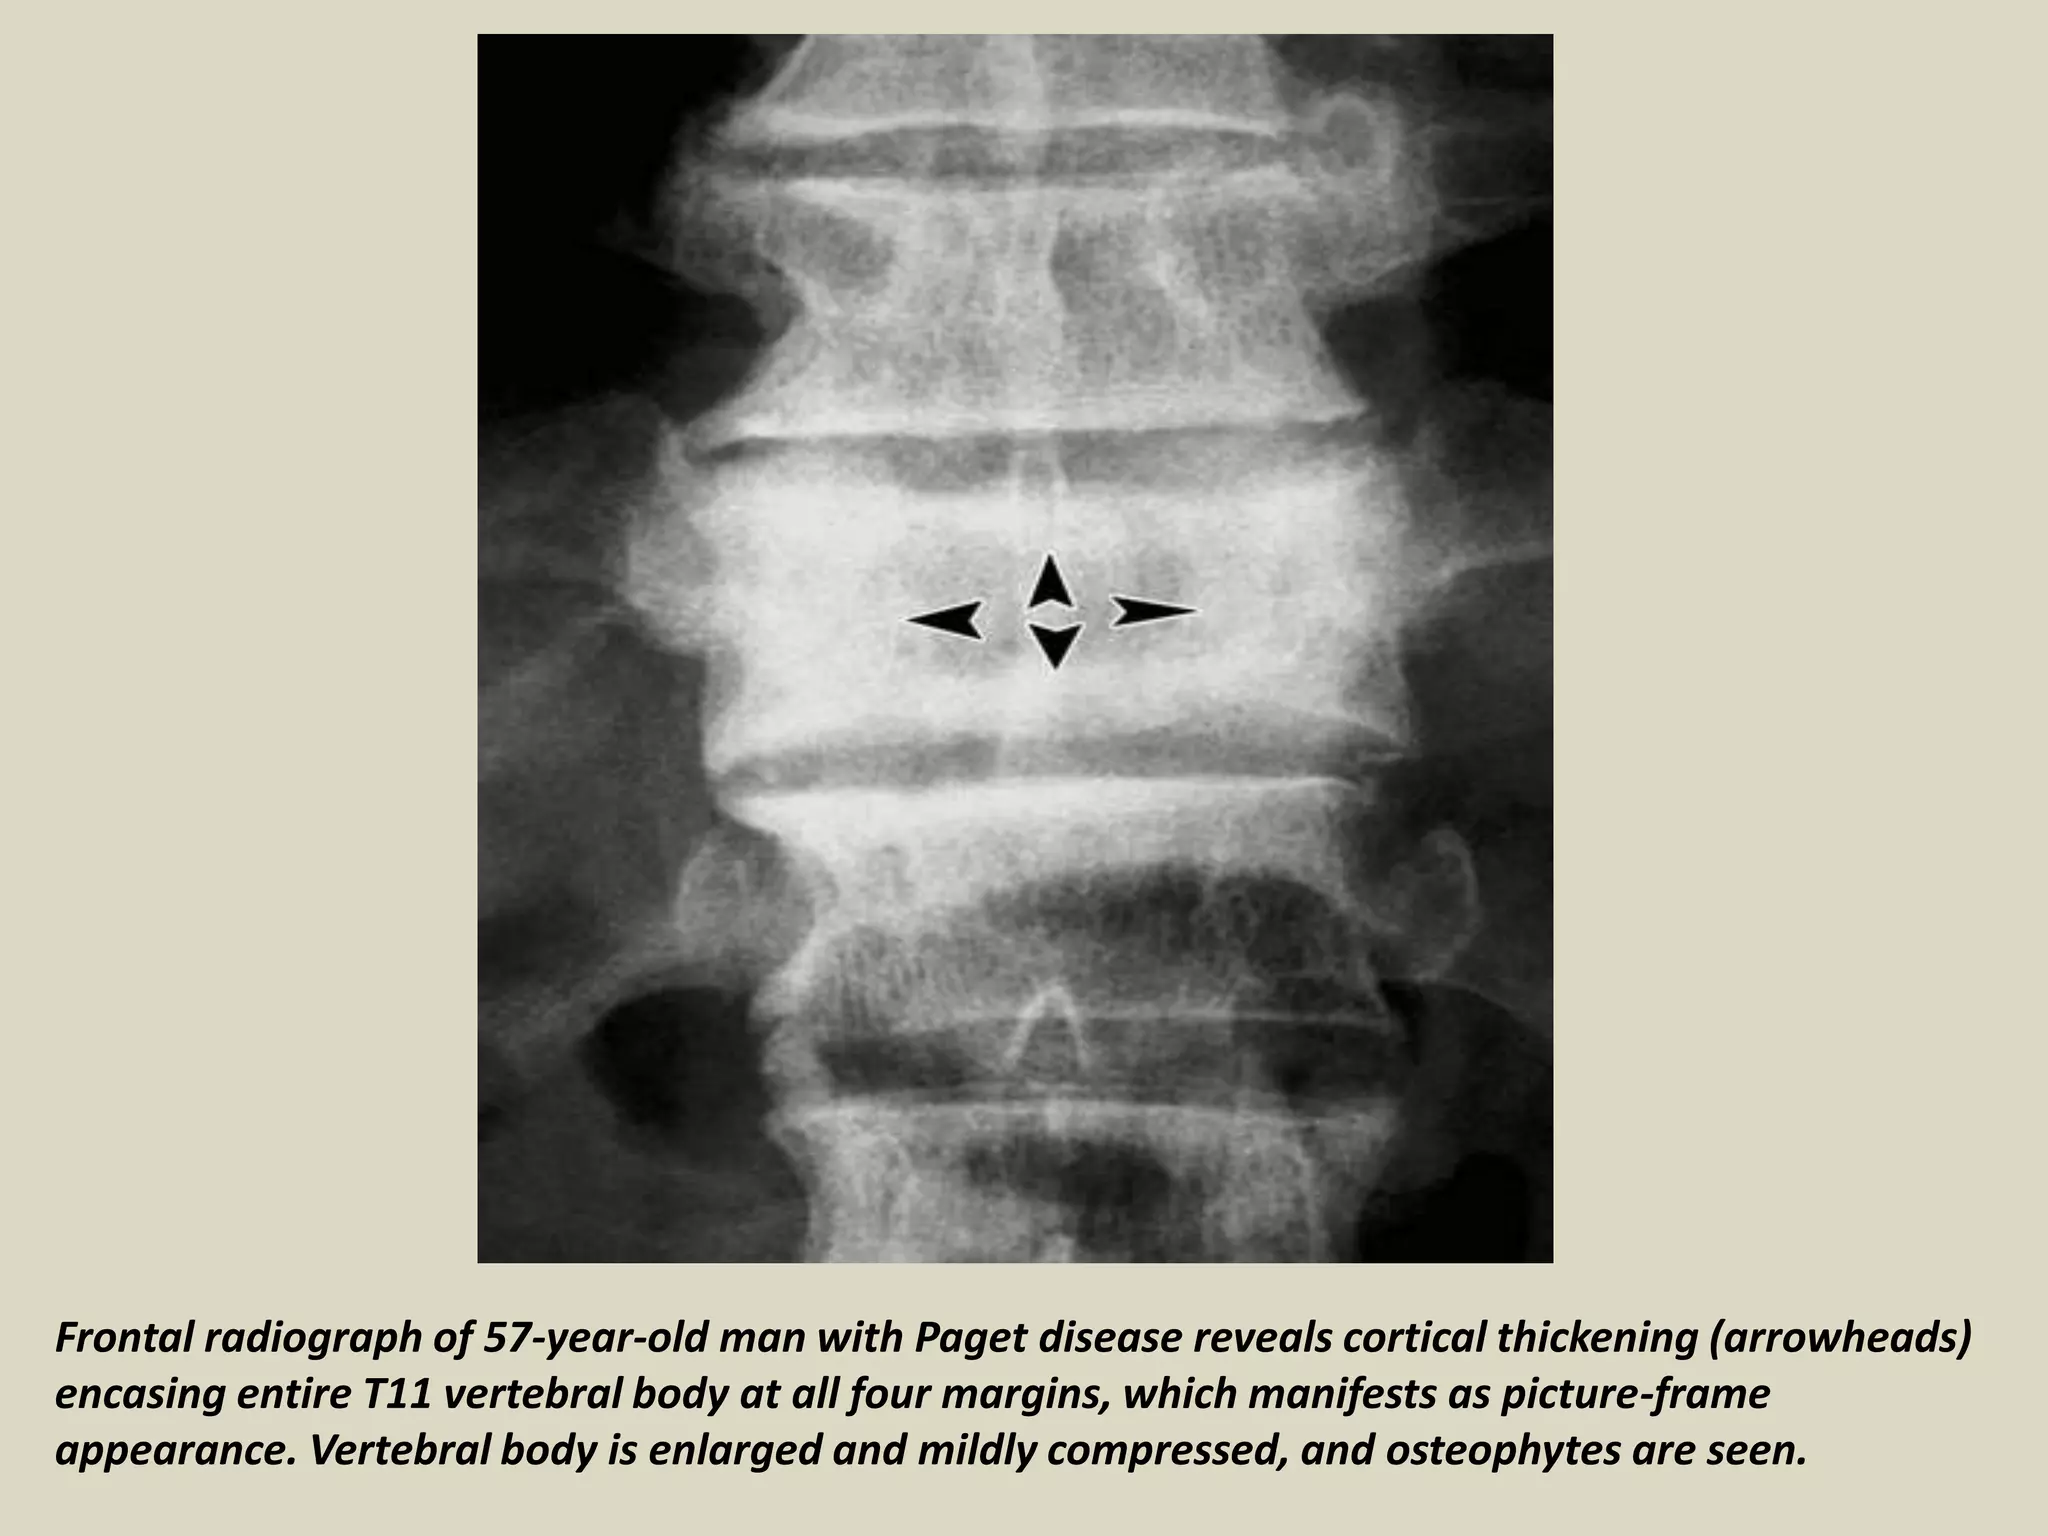

Frontal radiograph of 57-year-old man with Paget disease reveals cortical thickening (arrowheads)

encasing entire T11 vertebral body at all four margins, which manifests as picture-frame

appearance. Vertebral body is enlarged and mildly compressed, and osteophytes are seen.

Frontal radiograph of57-year-old man with Paget disease reveals cortical thickening (arrowheads) encasing entire T11 vertebral body at all four margins, which manifests as picture-frame appearance. Vertebral body is enlarged and mildly compressed, and osteophytes are seen.